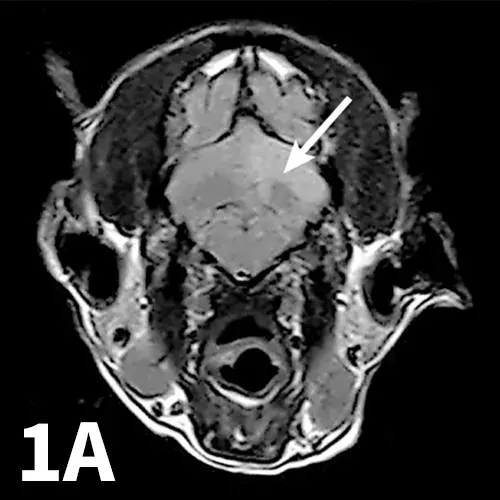

T2-weighted fluid-attenuated inversion recovery (FLAIR) transverse image showing well-demarcated hyperintensity (arrow) without apparent mass effect in the left cerebellar hemisphere (A). Apparent diffusion coefficient (ADC) map showing a coincident area of restricted diffusion (B; arrowhead).

The patient was anesthetized and magnetic resonance imaging (MRI) of the brain was performed. MRI showed a well-demarcated T2-weighted hyperintensity without mass effect in the left cerebellar hemisphere. This area was noncontrast enhancing and showed evidence of restricted diffusion on diffusion-weighted imaging (Figure 1). A cisternal cerebrospinal fluid tap was performed; results were within normal limits. These findings are most consistent with an ischemic event associated with the left rostral cerebellar artery. 1,2